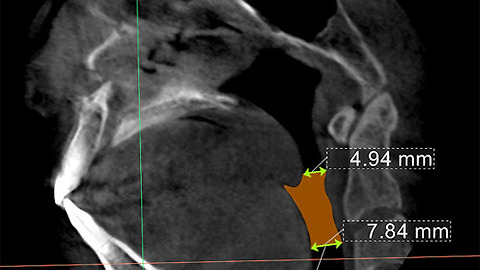

코를 골고 수면중 호흡의 끊기거나 멈추는 현상이 일어나게 된 근본적인 원인,

바로 기도가 (어떤 이유와 조건으로) 좁아졌거나, 좁은 것인데요.

코골이수술이 겨냥해야 할 지점도 바로 이 기도의 넓힘입니다, 정상인에 가깝게.

결정적인 영향이 되는, 그래서 치료의 포인트가 되는 부분은 기도확장입니다.